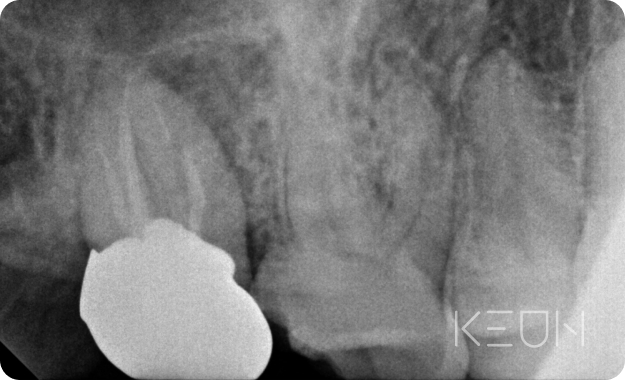

- Before

- After

신경 재치료

신경치료 근관의 개수, 길이, 굵기 등을 측정한 후 치수를 제거하고 근관을 세척해 미세한 근관까지 소독한 후 근관 충전을 하는 방식으로 치료합니다. 그러나 치료 후에도 지속해서 통증이 남아있다면 신경재치료가 필요합니다.